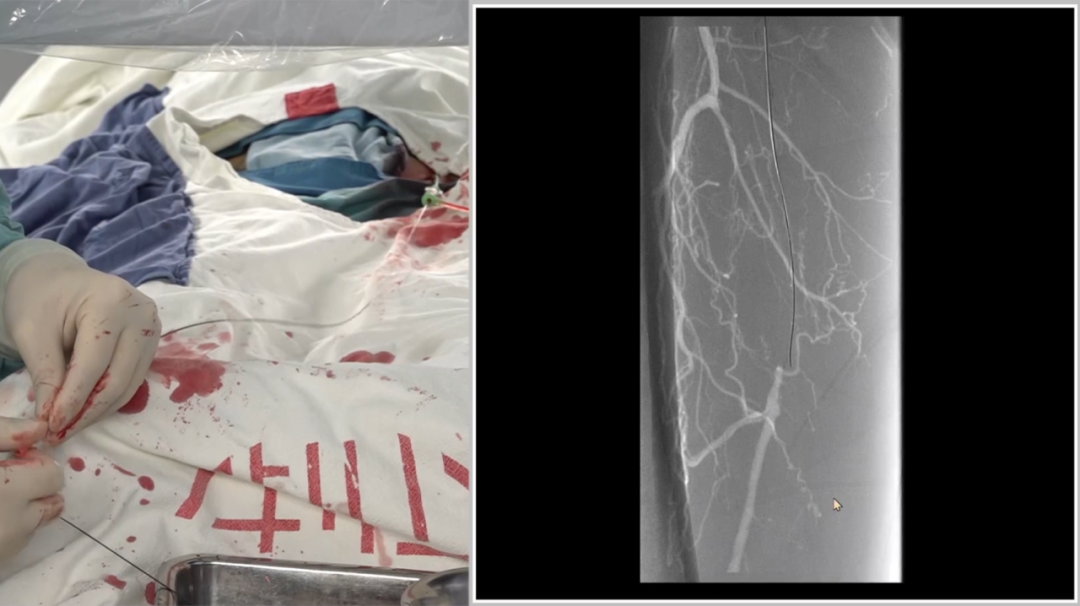

导丝突破:多种器械配合,应对坚硬病变

初始使用单弯导管配合Command18导丝尝试突破股动脉起始段纤维帽,未成功;

更换Terumo导丝后突破纤维帽,但支撑导管跟进困难,提示病变质地坚硬;

先后尝试Command 18、Treasure12 CTO导丝等,均难以顺利通过病变段;

关键技巧:采用"自制CTO导丝"——剪除V18导丝部分软头,塑形后利用其强支撑性,顺利通过病变并跟进支撑导管。